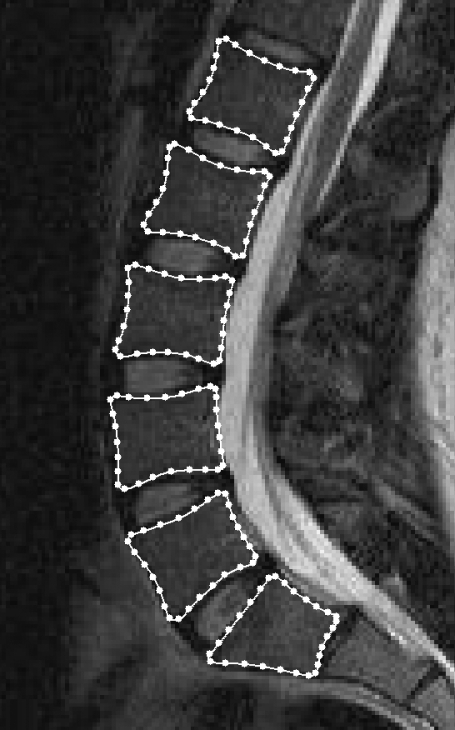

The model was created using the Active Appearance Modelling software tools from the University of Manchester, UK (http://www.isbe.man.ac.uk/∼bim/software/am_tools_doc/index.html). The model was defined by placing landmark points around the periphery of each vertebral body from L1 to S1 (Fig. 1). The same number of landmark points (28 per vertebral body, 168 in total) was used for each image and each point always referred to the same anatomical feature. After all of the 72 images had been marked (by one observer), the software aligned each set of points into a common co-ordinate frame by scaling, translating and rotating; this means that size differences and rigid body movements were removed from the model. The software then calculated the average position of the points (to give the average spine shape) and used principal component analysis to analyse the variation in their position. Principal component analysis is a statistical analysis method that can be used to reduce the dimensionality of a data set by identifying new, independent variables that describe patterns of variation. In the ASM, the new variables are called ‘modes of variation’ and are ordered such that the first one is the most important, describing the largest proportion of variance in shape, and the second and subsequent modes account for decreasing proportions of variance. The actual shape of the object in an image can thus be described using a linear combination of the modes of variation. This allows the shape to be quantified (using the coefficients of the modes of variation) in an efficient manner (using only the first, more important, modes). In the ASM, the values of the coefficients were assigned to each image and then transformed so that, for each mode of variation, the mean value was zero and the SD was unity. Two models were created, one using the images of the subjects in three different postures and another that also included the repeated scans in the standing posture.

Fig. 1.

Magnetic resonance image of the lumbar spine in the sagittal plane with 168 landmark points placed around the vertebral bodies from L1 to S1. These points were used to define the active shape model and were placed in consistent positions for all 72 images.